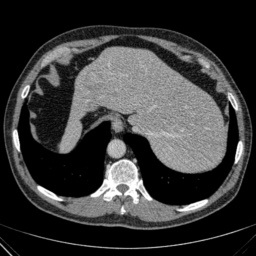

Refer to caption

(e) Normal Liver

(f) Normal Liver

(g) Liver Tumor

(h) Liver Tumor

Figure 4: We show some example brain MRI slices from BratS18 (first row) and Liver CT slices from LiTS (second row). Both normal- and abnormal-looking images are provided.

Aside from the difference in imaging tissue and modality of these two data sets, the tumor regions on the CT images are of different shape and size, as can be seen in Figure 4. Also, many CT scans are acquired in a way that introduces greater noise-like artifacts than MRI. For each dataset, 80%percent8080\% of randomly selected data are used for training and the resting 20%percent2020\% for testing.